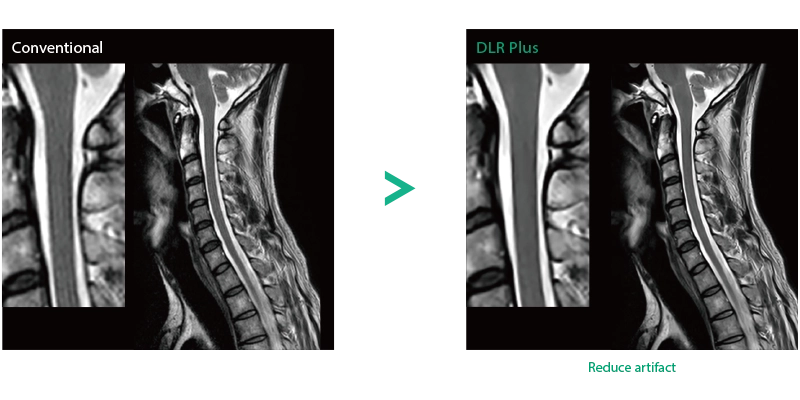

Deep Learning technology*8 enables image quality adjustment after imaging is complete. It optimize SNR and improve image sharpness by processing MRI signals in stages (k-space signal processing). This brings super-resolution and reduces truncation artifacts.

"DLR" is applicable to all body parts and promotes high speed imaging and diagnostic efficiency

IP-RAPID x DLR Plus can also shorten imaging time, allowing more images to be taken in the same examination time.